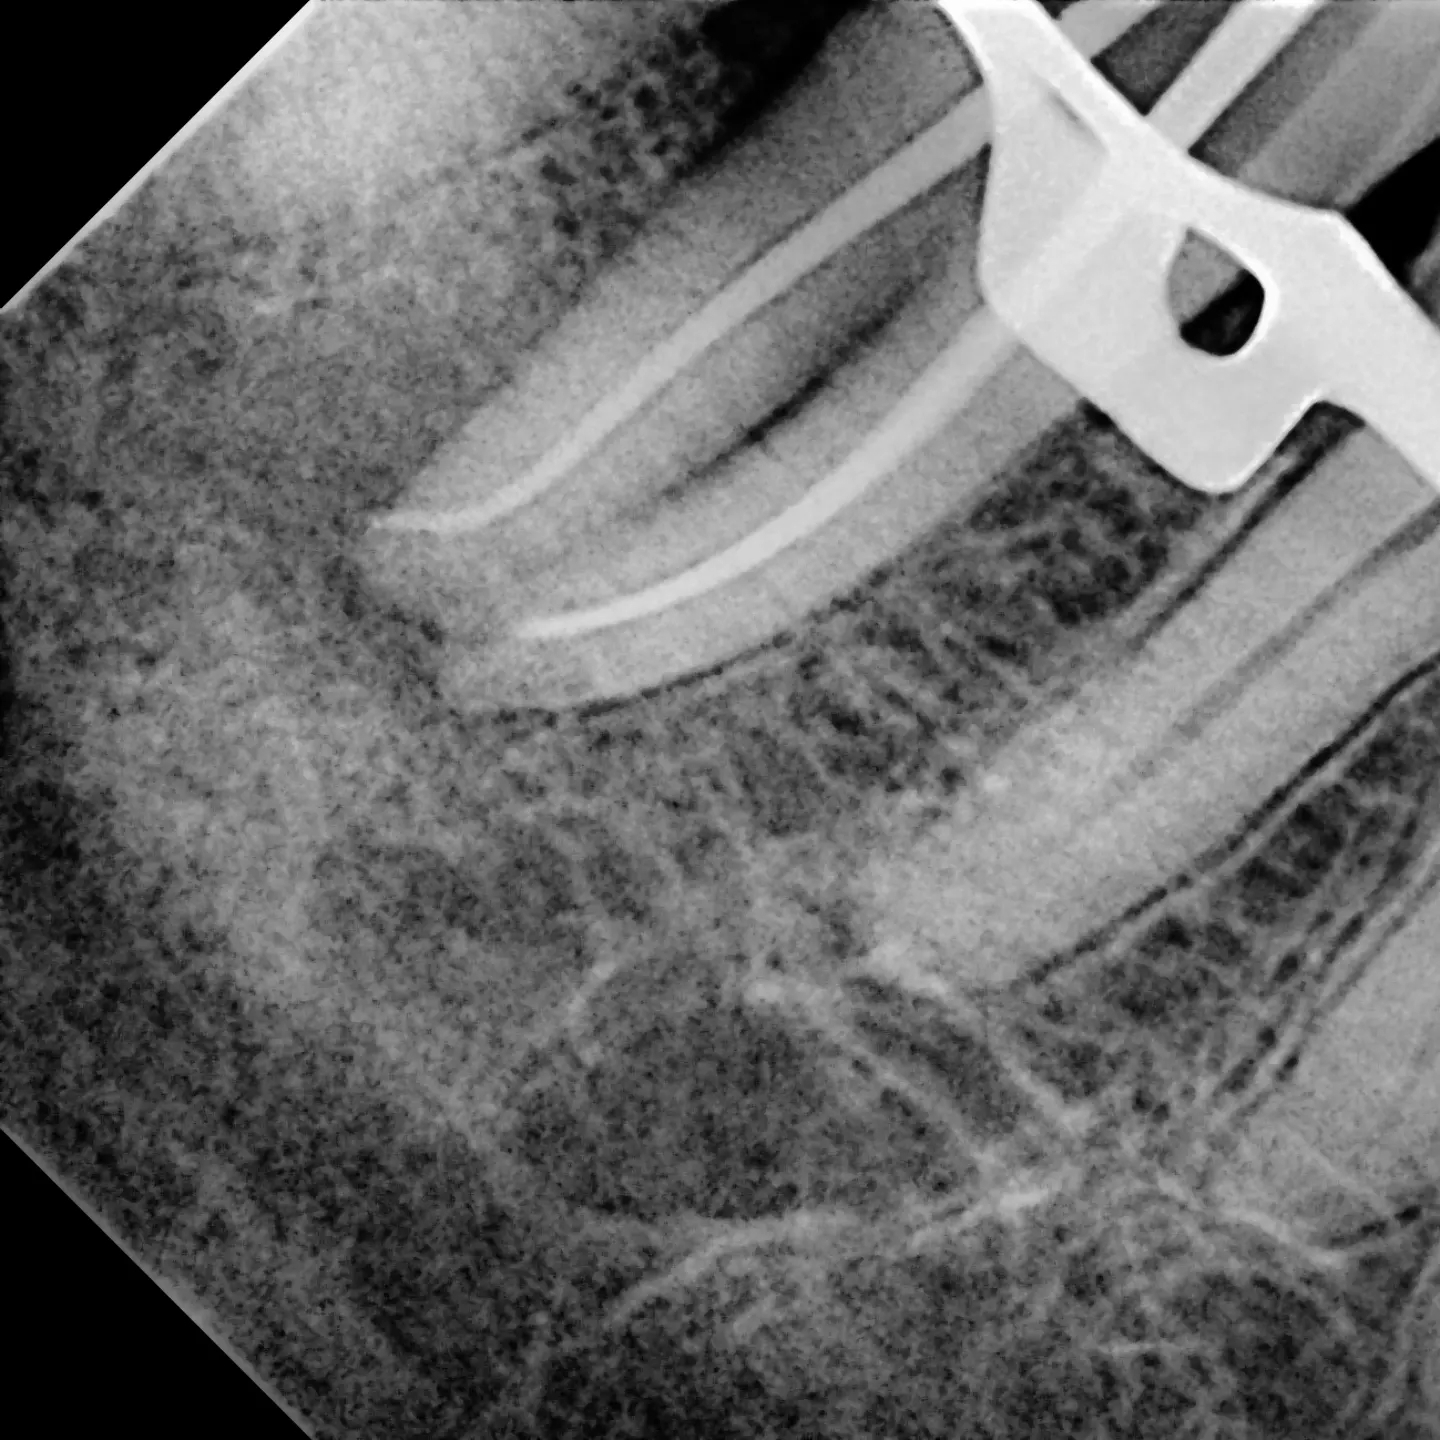

Endodontics perio-endo lower 7